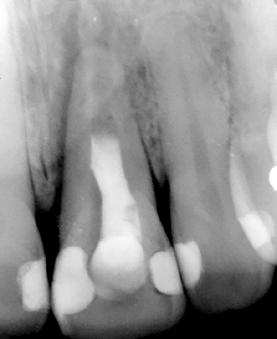

Figura 3. Radiografía de la zona que muestra el tratamiento previo de apiconformación realizado en el incisivo para lograr el cierre apical, actualmente fracasado. Se observa además una lesión quística asociada al ápice.

se realizó un tratamiento de apiconformación que, al momento de la revisión, mostraba signos de fracaso, con evidencia de infección y clínica sugestiva de fractura radicular (Figura 3).

Estos hallazgos confirman el éxito del procedimiento quirúrgico y de la posterior carga progresiva, con un mantenimiento óptimo de los tejidos duros y blandos a lo largo de más de dos décadas (Figura 15). Los cambios entre el momento inicial y el final del tratamiento son evidentes, especialmente al comparar la imagen intraoral de la primera visita con la tomada a los 22 años, donde la mucosa que rodea al diente 21 —y posteriormente al implante— se muestra engrosada, en buen estado de salud y con una estética destacable. Asimismo, la comparación entre la radiografía inicial, que evidenciaba el fracaso del tratamiento de conductos del diente en posición 21, y la radiografía a los 22 años, que muestra el implante sin pérdidas óseas asociadas, resulta elocuente (Figuras 16 a 19).